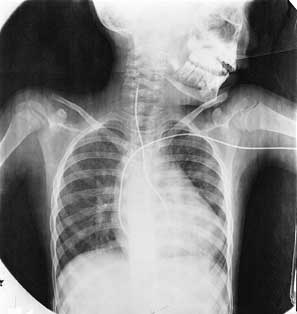

يحدث تصلب الشرايين التاجية عادة على مدى سنوات عديدة، رغم أن الأطباء وجدوا لُويحات في الشريان التاجي في بعض صغار السن من الجنود الذين قتلوا في المعارك. ولكن الأعراض غالبًا ما تظهر بعد سن الخمسين أو أكثر في بعض الأحيان. وتكون النوبة القلبية أولى الأعراض، وأحيانًا يحدث الموت المفاجئ. وعلى أية حال فإن الأعراض المبكرة المشابهة قد تكون ألمًا في الصدر يعقب تمارين رياضية أو أي نشاط آخر يجعل القلب يعمل أكثر من المعتاد. ويسمي الأطباء مثل هذا الألم بالذبحة الصدرية أو الذبحة. والشرايين التاجية الضيقة تغذي القلب بأكسجين أقل، مما يتسبب في الألم عندما يعمل القلب بطاقة أكثر. وبعد أن تتوقف التمارين أو ينتهي المجهود يتوقف الألم. وتزداد الذبحة إذا تركت من غير علاج، وغالبًا ما يشتكي المريض من ألم حتى وهو في حالة الراحة التامة. يشخص الأطباء أمراض الشريان التاجي بدراسة حالة المريض العامة والأمراض السابقة التي أصابته. ويسجلون تاريخ أي ذبحة أو نوبة قلبية أو وجود أي عوامل خطر. وقد يكشف الفحص العام عن وجود أسباب وعوامل خطر مثل ارتفاع ضغط الدم أو عطب في القلب. يستعمل الأطباء آلة تسمى مرسمة كهربائية القلب لمعرفة أي عطب في القلب أو أي اضطرابات في انتظامه. وتعطي هذه الآلة تخطيطًا يسمى رسم كهربائية القلب، يوضح النشاط الكهربائي لعضلة القلب. وتسجل الدفعات على ورق متحرك يوضح نشاط القلب الكهربائي على شكل سلسلة من الخطوط المموجة أو المتعرجة. وتمثل التعرجات الأساسية انقباض البطين والتعرجات الفرعية تمدد البطين وانقباض وتمدد الأذين. وتؤخذ معظم رسومات القلب للمريض وهو مستلقٍ، ولكن بعض الأطباء يرسم القلب للمريض وهو يؤدي بعض التمارين الرياضية. ومثل هذا التخطيط يوضح ما إذا كان القلب مريضًا حتى وإن لم يشك المريض من ألم، ويوضح إذا كان القلب يتلقى كمية كافية من الأكسجين أثناء التمارين الرياضية القاسية أم لا. يستعمل الأطباء أيضًا طريقة أخرى تسمى التصوير النَّوَوي الشُّعاعي، لتعرف مرض الشريان التاجي. يحقن الطبيب مادة مشعة في دم المريض ويستطيع أن يرى المادة على شاشة أثناء انتشارها في عضلات القلب. والمساحة التي لا تتلقى دمًا تظهر خالية على الصورة. ويستعمل الأطباء التصوير النووي الشُّعاعي عادة مع رسم كهربائية القلب تحت الإجهاد. وإذا كان هناك شك في أسلوب التشخيص العادي فإن الأطباء قد يفضلون القثطرة القلبية، ثم يعقبها تخطيط الأوعية التاجية. وهنا يدخلون أنبوبًا مرنًا طويلاً يسمى القثطار عن طريق وعاء دموي كبير عادة ما يكون شريانًا في منطقة التقاء الفخذ مع الجذع، ويدفعون القثطار إلى حيث يبدأ الشريان التاجي ويحقنون صبغة. بهذه الطريقة يمكن رؤية الشرايين من الداخل ـ ويمكن تسجيلها على فيلم أشعة سينية وتسمى الصورة الوعائية. وهذا الاختبار يُظهر حالة الشرايين التاجية بوضوح. وقد توضح الصورة الوعائية للشريان التاجي وجود إصابة طفيفة أو ربما الموت في بعض الأحيان. ولهذا يجريها الأطباء فقط في الحالات التشخيصة المعقدة.

التشخيص والعلاج

حينما يصل مريض النوبة القلبية للمستشفى يجري الأطباء رسمًا وتخطيطًا للقلب ليتأكدوا من أن المريض يعاني فعلاً النوبة القلبية وليس مجرد ألم في الصدر ناتج عن خلل أو اضطراب آخر. فعضلة القلب المصابة تحدث موجات غير عادية في رسم القلب التخطيطي. ويلجأ الأطباء أيضًا إلى بعض التحاليل الطبية للدم. ولكن التحاليل في هذه الحالة ليست مفيدة إلا إذا مضت ست ساعات على النوبة القلبية. وإذا استمر المريض يشكو من الألم فإن الطبيب في هذه الحالة قد يصف مسكنًا للألم مثل المورفين. ويستخدم الأطباء أيضًا أدوية وعقاقير يمكن أن تذيب الجلطة في الشريان المسدود. وإذا فشل العقار في أن يذيب الجلطة فإنهم يلجأون لإسعاف مستعجل بتصوير الأوعية القلبية أو إجراء جراحة المجازة. وبعد إدخال مريض النوبة القلبية للمستشفى تتم مراقبة أي مضاعفات مثل هبوط القلب واللانظمية أو اختلال ضربات القلب في وحدة العناية المركزة. ويحدث هبوط القلب عندما لا يضخ القلب كمية كافية نتيجة لتلف بالغ في عضلة القلب، ويمكن علاجه بنجاح. وفي حالة اللانظمية، يحدث نظام القلب الكهربائي إيقاعًا غير عادي. ويحدث أحد أنواع اللانظمية ـ وهو الرجفان البطيني ـ عندما ترسل إشارات كهربائية من البطين بغير انتظام. وقد ينتج إيقاع القلب غير الفعال، والموت المفاجئ عن الرجفان البطيني. واللانظمية يمكن علاجها طبيًا. وقد تصل نسبة الموت في مرضى النوبة القلبية الذين لا يتلقون علاجًا طبياً إلى أكثر من 20%. وبعضهم يموت قبل أن يصل الطبيب، ويتجاهل بعضهم الأعراض. وتتراوح نسبة الموت في المرضى الذين يتلقون العلاج بالمستشفيات بين خمسة وعشرة في المائة. وقد يتعرض مرضى النوبة القلبية الذين يشكون من ألم متكرر في الصدر أو اللانظمية، أو هبوط قلبي، للإصابة بأمراض أخرى أكثر من المرضى الذين لا يشكون من هذه الأعراض.